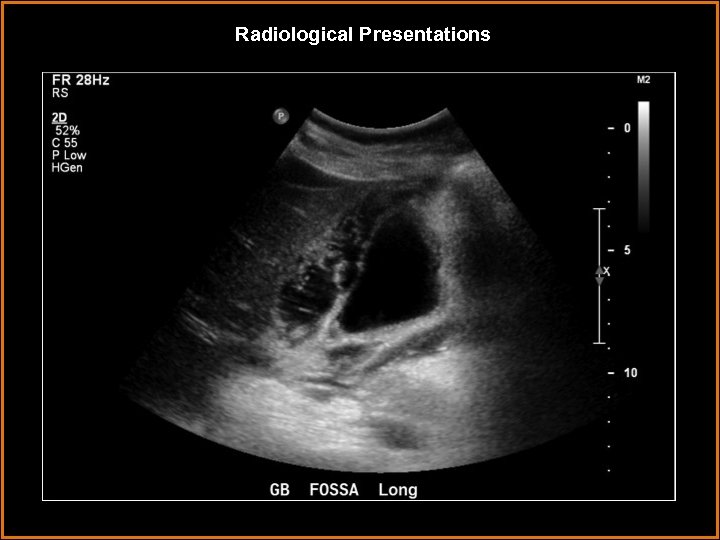

Findings and Differentials Findings: Striated thickening of the gallbladder wall with multiple hyperechoic, serpentine Findings and Differentials Findings: Striated thickening of the gallbladder wall with multiple hyperechoic, serpentine bands separated by hypoechoic areas. Also, intraluminal membranes concerning for desquamative mucosa. Differentials: • Acute cholecystitis – Wall thickening and pericholecystic fluid are neither sensitive nor specific. The most sensitive finding is a gallbladder stone with a positive Murphy’s sign. • Hydatid cyst – intrahepatic cystic lesion with floating membranes or multiseptated cysts. • Emphysematous cholecystitis – dirty shadowing from gas in gallbladder wall. • Volume overload – usually uniform, homogeneous wall thickening.

Discussion • Gangrenous cholecystitis is on the severe end of the spectrum of acute Discussion • Gangrenous cholecystitis is on the severe end of the spectrum of acute cholecystitis. • It is thought to be a result of tension in the gallbladder wall secondary to increased distention. This results in ischemic necrosis of the gallbladder wall, sometimes due to cystic artery thrombosis. • The condition occurs in older patients, usually male. Coexisting vascular disease is commonly seen. Sonographic Murphy’s sign is usually absent, thought to be due to devascularization and denervation. • On ultrasound, the primary finding is layered or striated gallbladder wall thickening. Usually, it is irregular with luminal projections. Less often seen, but more specific, are intraluminal membranes that are thought to represent desquamative mucosa.